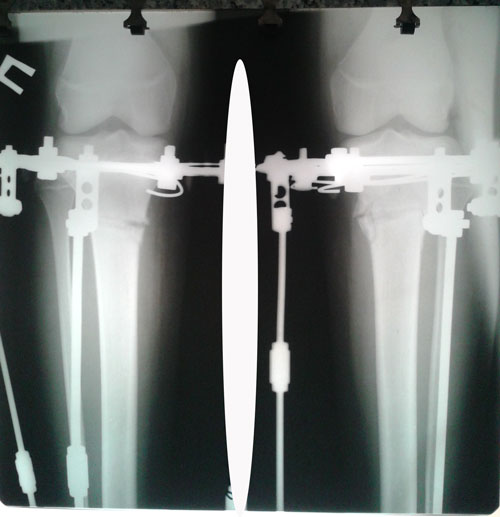

Рентген на фиксации.

20160709_124650.jpg

20160709_124636.jpg